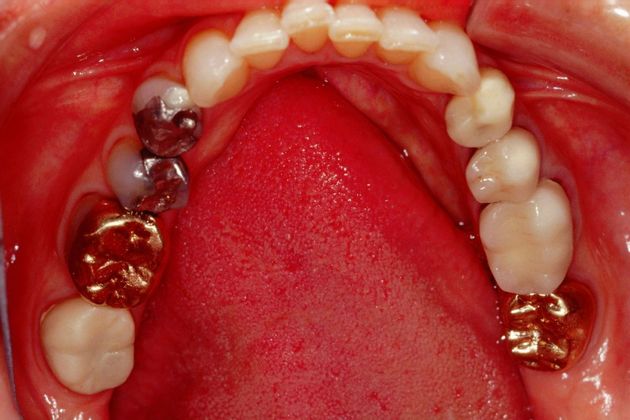

Procedures; TMJ CAT scan, TMJ deprogramming, whitening, sedation dentistry, reconstruction of all the back and upper front teeth with porcelain crowns, bite guard therapy. This foster care provider wanted to be free of the pain in her jaw joints. She had a lifelong history of grinding, many of her back teeth were breaking down and her bite was off. Her treatment was performed in sections to spread out the cost. She and her husband were so pleased with the result!